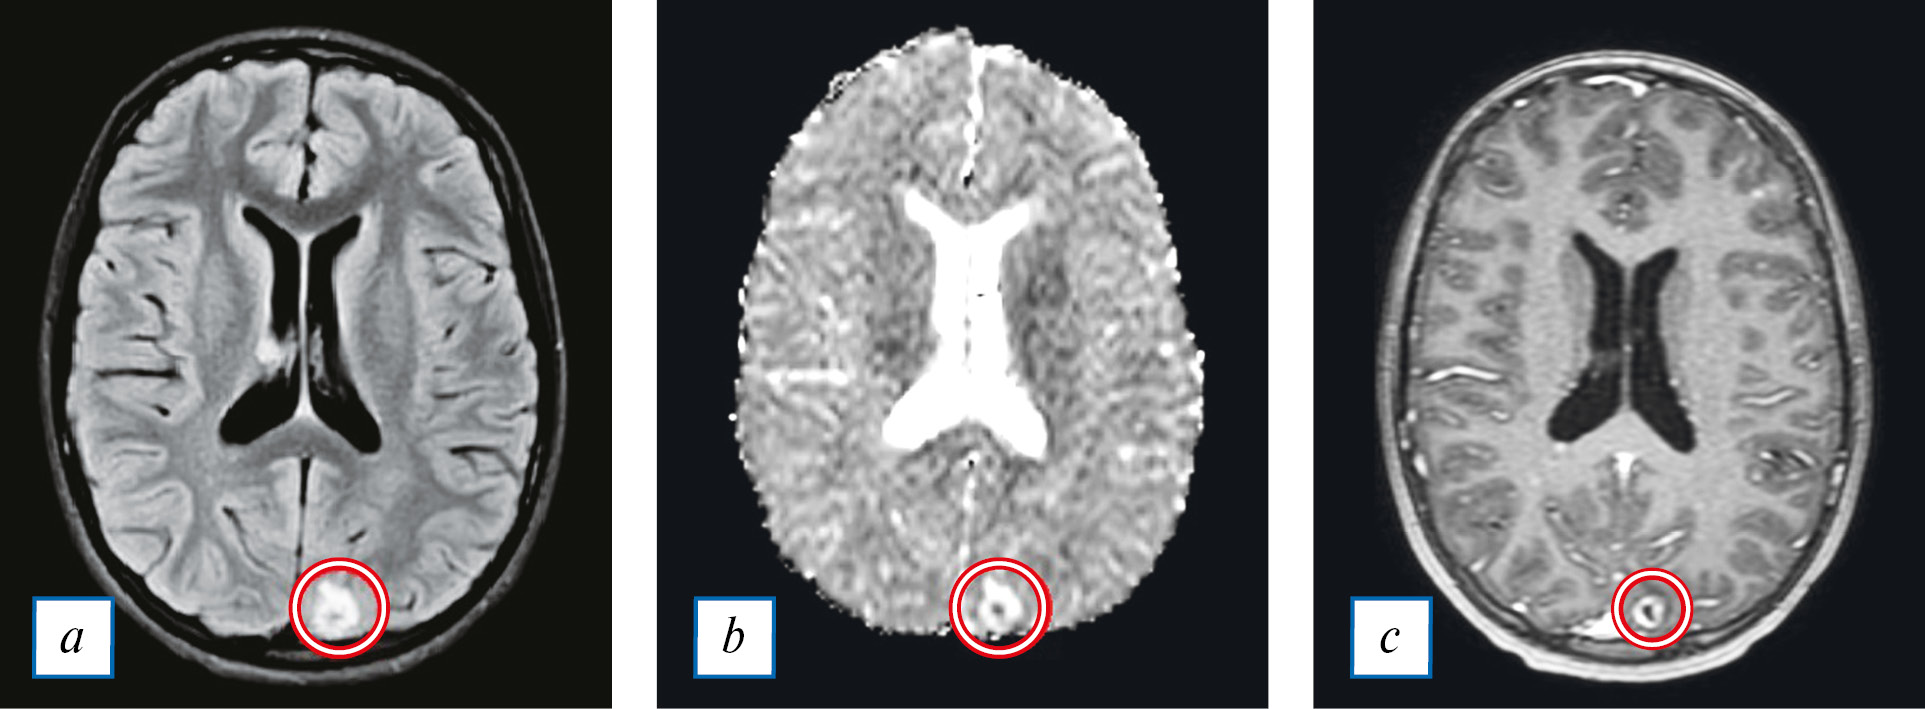

Некроз обычно располагается в центральной зоне поражения и имеет истинное ограничение диффузии на DWI. Сначала поражение проявляется в виде диффузного или узелкового усиления, после этого развивается центральный некроз с формированием утолщенного кольцевидного усиления в капсуле абсцесса (рис. 3). Когда формирование капсулы завершено, абсцесс проявляется в виде округлой или яйцевидной области, что можно визуализировать также и на преконтрастных КТ-изображениях [28].

Рис. 3. МРТ головного мозга ребенка с клинически подтвержденным бактериальным эндокардитом (обведено красным): a — FLAIR (абсцесс в левой затылочной доле); b — карта измеряемого коэффициента диффузии (ограничение диффузии от содержимого абсцесса); с — Т1-ВИ с внутривенным контрастированием (накопление контрастного препарата стенкой абсцесса).

Fig. 3. Brain MRI of a child with clinically confirmed bacterial endocarditis: a — FLAIR (abscess in the left occipital lobe); b — ADC mape (restriction of diffusion from the contents of the abscess); с — T1-weighted brain MRI with contrast (contrast enhancement in the abscess wall).